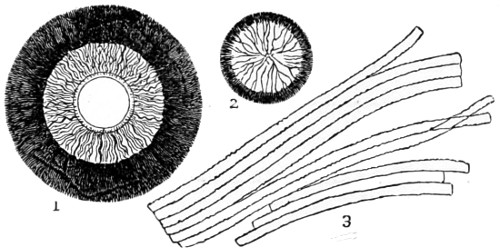

Fig. 1. a. Spheroidal epithelium cells, filled with central nuclei and granular matter; b. mucous membrane of stomach, showing cells, with open mouths of tubes at the bottom of each, magnified 50 diameters—2. a. Diagram of a portion of the involuted mucous membrane, showing continuation of its elements in the follicles and villi, with a nerve entering the submucous tissue. The upper surface of one villus is covered with cylindrical epithelium; the other denuded, and with dark line of basement membrane running around it; b. epithelium cells, separated and magnified 200 diameters, a central nucleus, with a nucleolus, seen in centre; c. pavement epithelium cells, from the mucous membrane of bronchial or air tubes with nuclei, and nucleoli in some; d. vibratile or ciliated epithelium, nuclei visible, and cilia at the upper free surface, magnified 200 diameters—3. a. is one of the tubular follicles from a pig’s stomach, cut obliquely to display upper part of cavity, and the cylindrical epithelium forming its walls, a few cells detached; b. shows a section of a lymphatic, with capillary blood-vessels, distributed beneath the mucous surfaces—4. Cells of adipose tissue, or fat, magnified 100 diameters—5. a single fat-cell separated, and magnified 250 diameters—6. A capillary of blood-vessels distributed through tissue—7. Section of the Tendo-Achillis as it joins the cartilage, showing stellate cells of tendon, seen to be gradually coalescing to form round or oval cells of cartilage—8. A vertical section of cartilage, with clusters of cells arranged in columns previous to their conversion into bone—9. A small transverse section of the same, showing the gradual change of the cartilage cells at a. into the true bone cells, lacunæ, at b. with characteristic canaliculi—10. A stellate nerve corpuscle, with tubular processes issuing forth, at a. filled with corpuscles containing black pigment, above which is a corpuscle the nucleus of which is seen to have nucleoli; at b. a corpuscle xxiv enclosed within sheath, and filled with granular matter taken from the root of a spinal nerve—11. The continuity of muscle, the upper portion, with connective tissue of the lower portion, from the tongue of a lamb—12. Branched muscle, ending in stellate connective cells, from the upper lip of the rat—13. Choroidal black pigment-cells from the human eye.